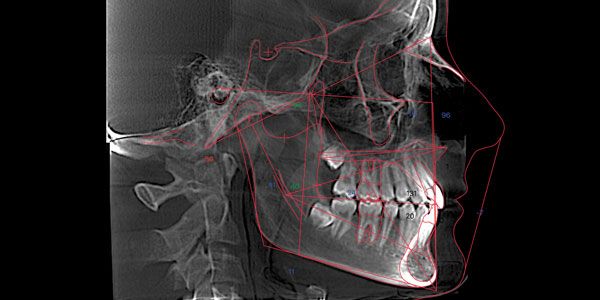

Dr. Robert Kaspers discusses the effect that the musculature and the occlusion have on the condylar position For years, orthodontists have utilized two-dimensional radiographs to treatment plan their orthodontic treatment. Fortunately, the advent of cone-beam computed tomography (CBCT) allows an orthodontist to take a “functional” radiograph, so the condylar position can be evaluated, and an […]